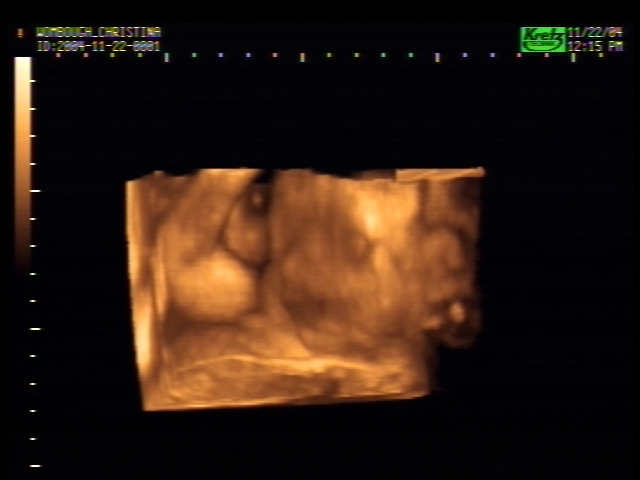

3D Sonogram Pictures

Click on a picture to make it bigger!